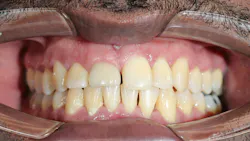

- Labialization of the dental implant, especially in the maxillary anterior region (figure 1)

- Open contacts due to tooth migration, and cervical margin discrepancies in gingival height4 (figure 3)